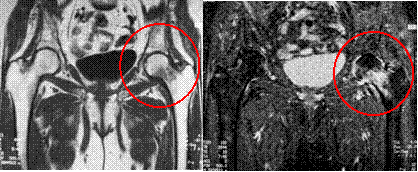

Occult femoral neck fracture